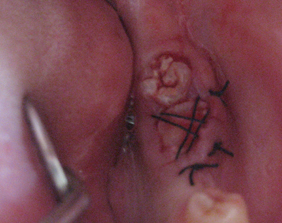

縫合と固定

移植歯を移植床にしっかりと固定します。